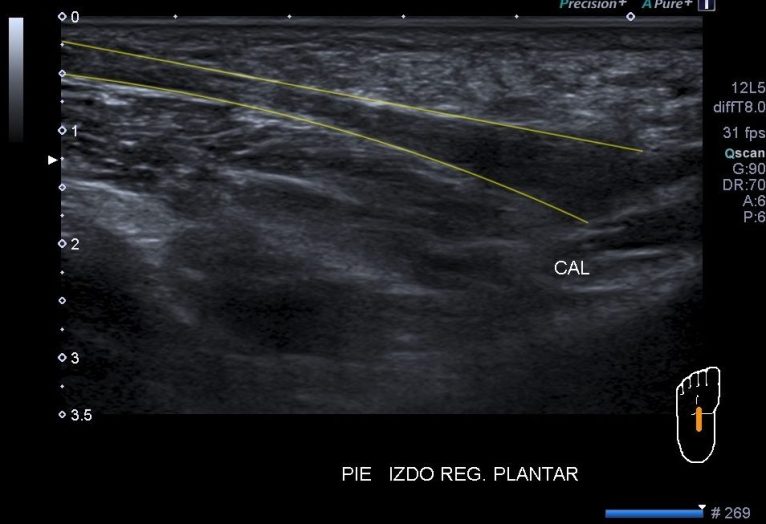

Me llama poderosamente la atención, lo recuerdo perfectamente, la normalidad del recto anterior, pero después de buscar un poco observo como el vasto intermedio si está «distinto», algo heterogéneo, voy a comparar con el lado contralateral y bingo¡ el vasto intermedio, que es de esa musculatura «que nunca tiene nada», modo «ironía on», te sorprende…y la ecografía muscular es como el océano, nunca puedes confiarte…

Mira las imágenes y tu misma te darás cuenta:

La zona que presenta mayor abombamiento y empastamiento (cara lateral del muslo izquierdo), se visualiza aumento del grosor del fascículo muscular correspondiente con el vasto intermedio, sin poder evidenciarse la presencia de lesiones definidas. El diagnóstico es un aumento difuso e inespecífico del Vasto Intermedio, sin masas ni roturas. A valorar con RMN.